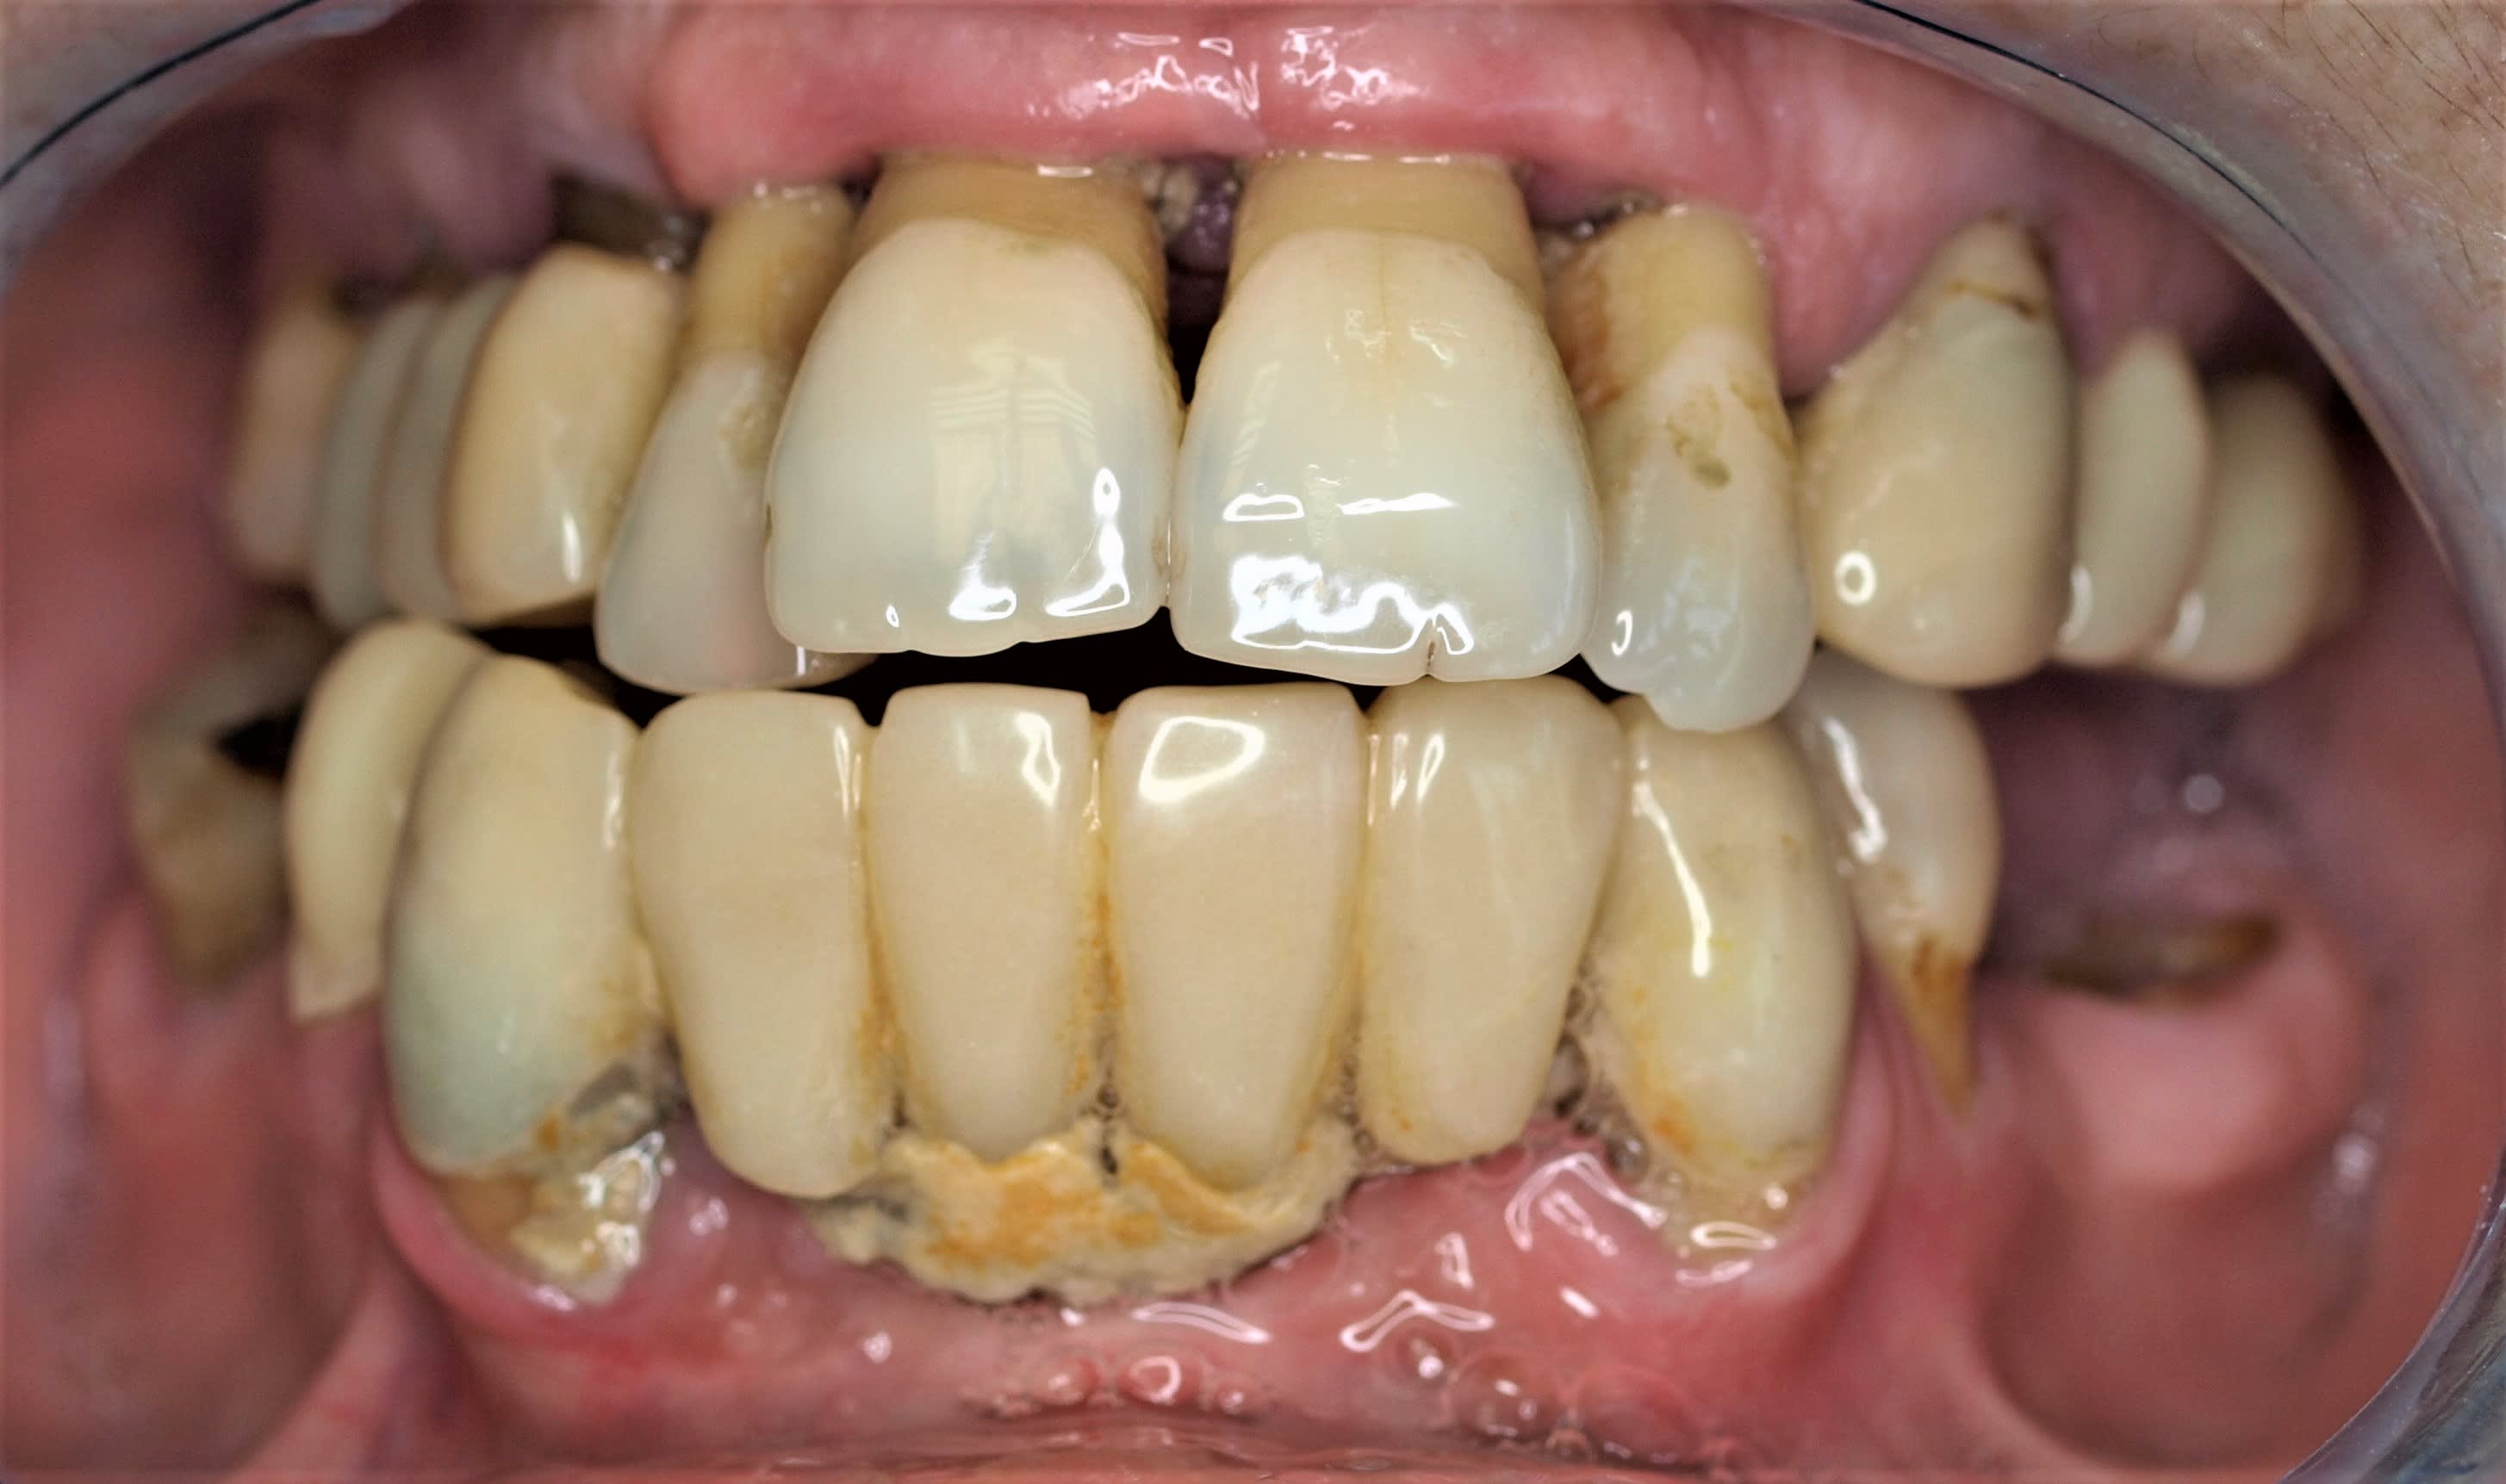

Patient 50 ans, parodontite chronique, venu consulter pour sa 15 mobile.

Que préconiseriez vous?

regardes ce cas , je lui ai fait un bridge complet zircon haut et bas . la photo date de 2010 et les bridges sont tjs là !